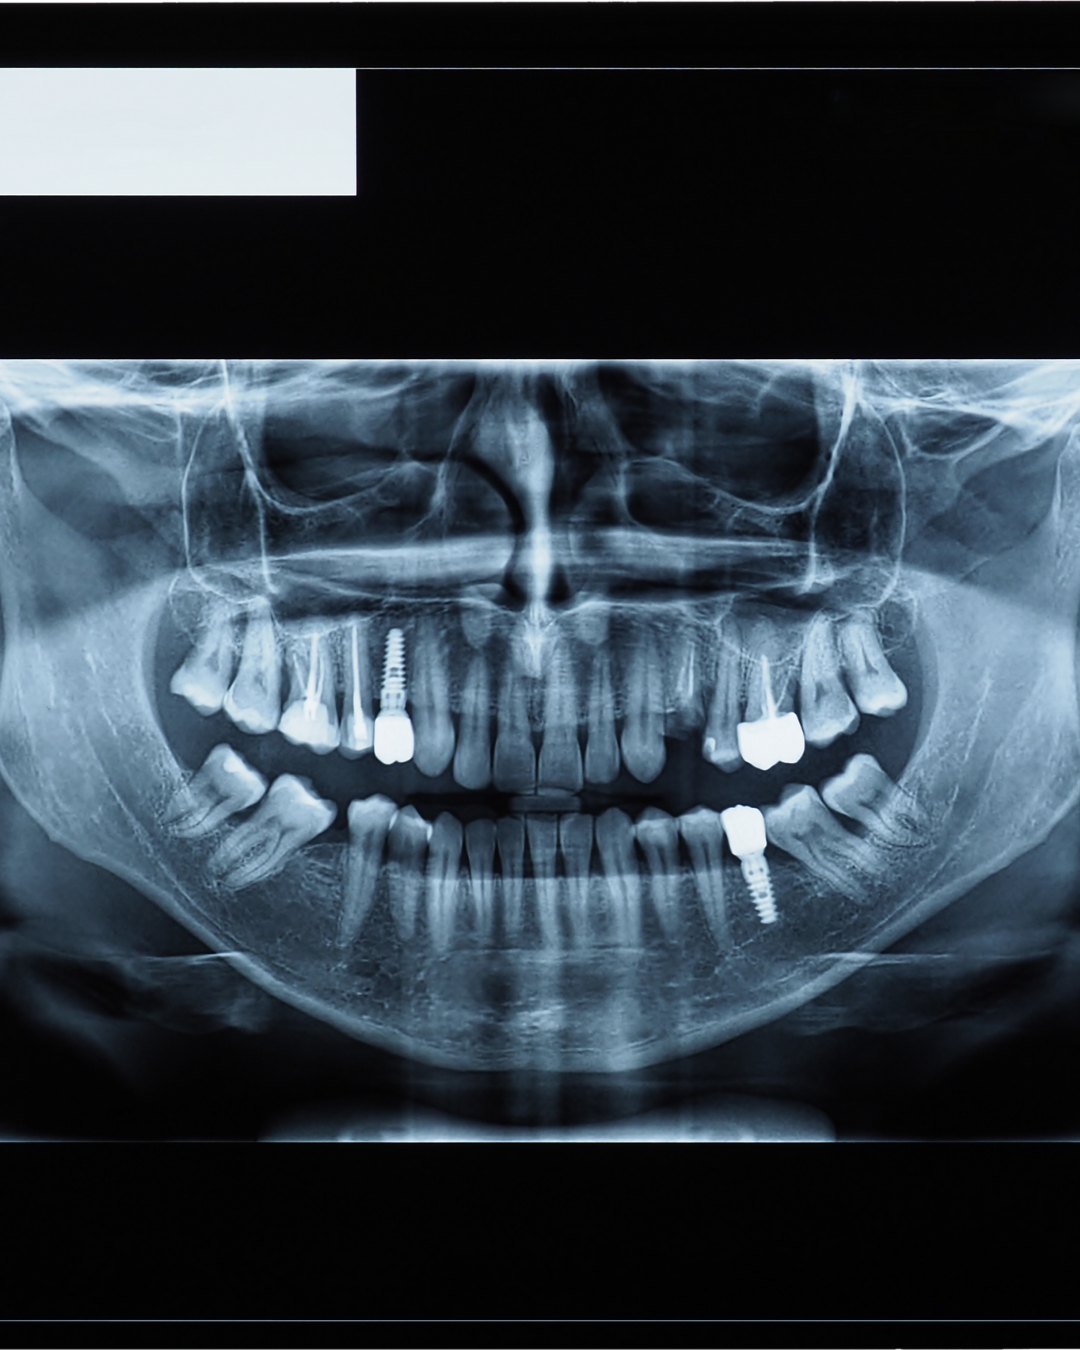

This 1.5-day on-site course is dedicated to surgical protocols for sinus elevation procedures. Content includes anatomical assessment, indications for lateral and transcrestal approaches, grafting material handling, complication management, and radiographic planning using CBCT evaluation. Teaching is based on clinical case analysis and step-by-step surgical demonstrations.